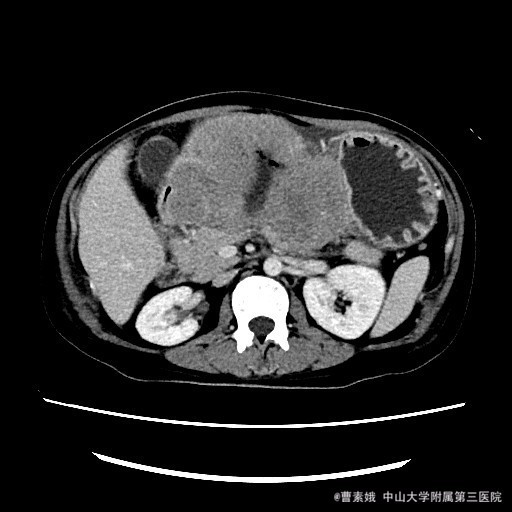

患者:女 37岁 主诉:发现腹部包块伴恶性、呕吐1月余 病史:患者平素一直有胃部不适,偶有胃痛、饱胀感不适,一直口服药物治疗,未见明显好转,1月前自觉腹部包块,并出现恶性、呕吐。呕吐为胃内容物。

查体:左上腹触及一包块,较柔软,余未特殊。 辅助检查:全腹CT平扫+增强示:胃体至胃窦部胃壁弥漫性增厚并软组织肿块,考虑淋巴瘤可能性大。

入院诊断:胃淋巴瘤(?) 治疗:诊断:胃淋巴瘤(?) 治疗:入院后(胃部肿物)送检组织镜下见胃粘膜固有层及肌层结构破坏,并见中等偏大异形淋巴样细胞弥漫浸润,局部成片分布,细胞具有异型性,可见核仁,核分裂象易见,结合免疫组化结果,符合高级别B细胞源性淋巴瘤,考虑滤泡淋巴瘤(FL3b)。组织少,肿瘤成份少,不完全排除弥漫大B细胞性淋巴瘤(生发中心亚型)。建议结合临床。排除手术禁忌症后,于腹腔镜下胃大部分切除术 。 术程顺利,患者恢复较好,建议其进一步化疗,患者表示拒绝后出院。